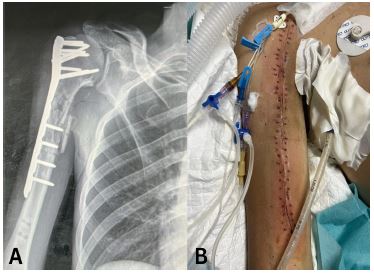

A 43-year-old male presented with multiple injuries sustained from a bomb explosion. He had a head injury and a Glasgow Coma Scale (GCS) score of 8, a chest injury with haemopneumothorax, and a Gustilo-Anderson Grade IIIB open fracture of the right proximal humerus with no signs of neurovascular injury of the right upper limb. He was intubated in the ED and subsequently underwent a craniotomy, bilateral intercostal chest tube insertions, and Open Reduction Internal Fixation (ORIF) of the humerus. This ORIF failed due to an inappropriate plate length and was later revised on another occasion with the correct plate followed by soft tissue repair and covering of the bone and plate with a SSG. The intercostal tube was removed after 6 days. He was admitted to the Intensive Care Unit (ICU) for 4 weeks after which weaning from mechanical ventilation was successful and he was transferred to a normal word.

Figure 2: (A) Anteroposterior view radiograph of the fracture and internal fixation. (B) Clinical photograph of the healed wound.